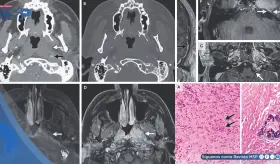

El linfoma NK estaba localizado en el seno maxilar izquierdo, con edema inflamatorio circundante.

El linfoma extraganglionar de células NK/T es un subtipo raro de linfoma no Hodgkin que afecta principalmente a la cavidad nasal y otras áreas distintas a los ganglios linfáticos.